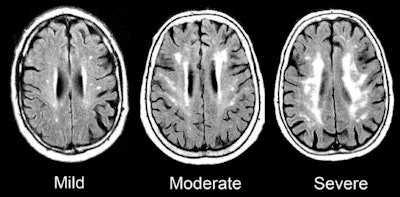

MRI scans show damage to the brain's white matter. Images courtesy of the Gottesman Lab.Overall, increasing and chronic inflammation were associated with the most damage to white matter; therefore, there is reason to infer a cause and effect relationship between growing and persistent inflammation and evidence of dementia, according to Walker. The researchers stopped short of saying their results were conclusive, however.